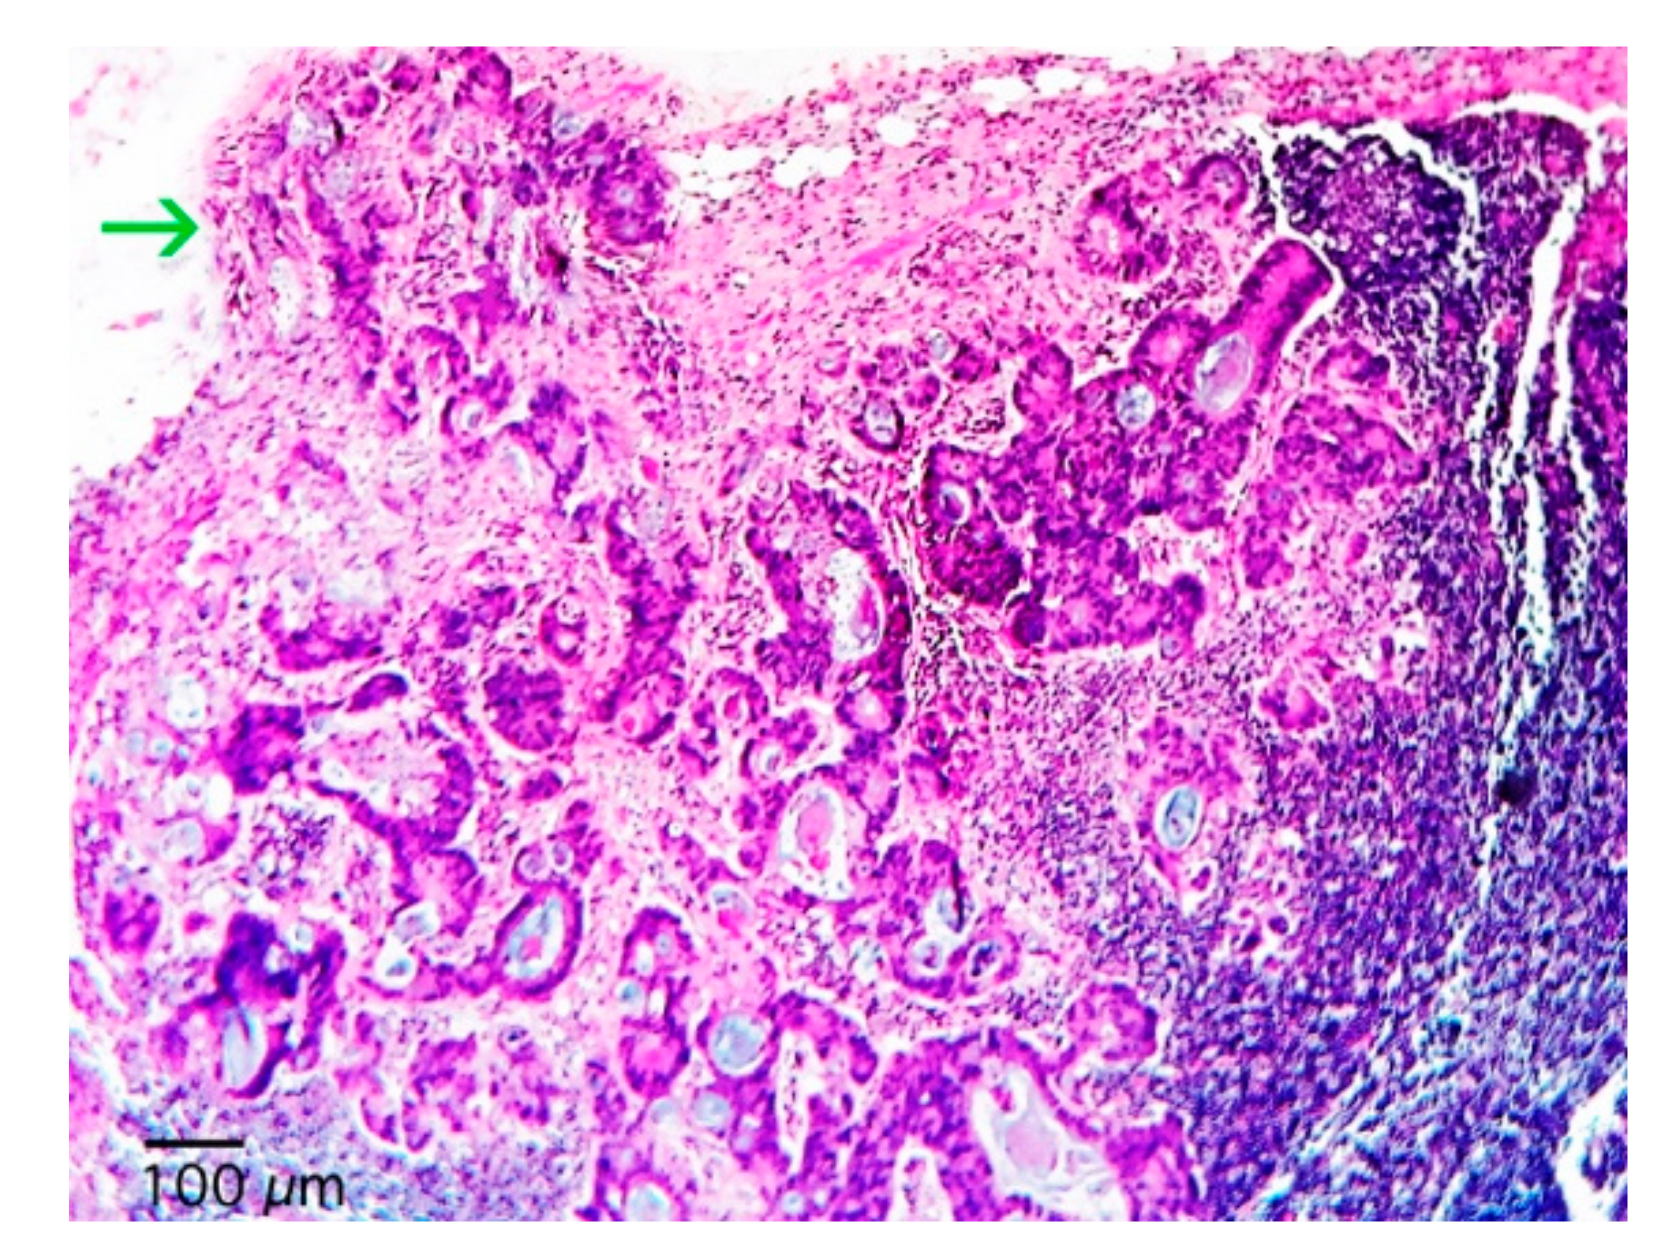

| Extracapsular Extension - No (%) | |

| No | 82 (65.1) |

| Yes | 44 (34.9) |

| Extracapsular Extension | |||

| No | 81.2 | 84.1 | 0.320 |

| Yes | 63.9 | 86.5 |